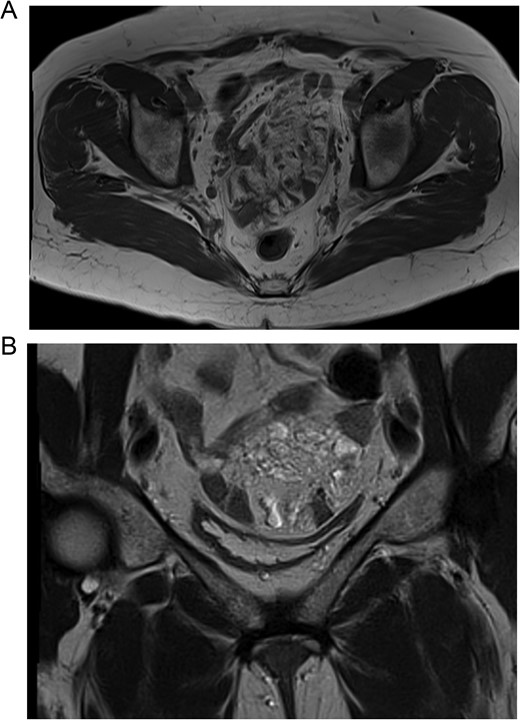

(A) MRI, the lymphangioma is seen close to the vaginal cuff and the pelvis. (B) MRI, the lymphangioma is seen arising from the mesentery of the small bowel.

To further asses the mass and have a surgical plan, a magnetic resonance imaging (MRI) revealed in the T2 sequence that the mass was close to the vaginal cuff and arose from mesentery of the bowel. It was multilocular, heterogeneous, had hyperintense contours, and included septations and small cystic areas. All other laboratory analyses were normal, and due to these findings, enteric cysts, myomas, neoplasms, abscesses, and sarcomas were among the differentials. Therefore, surgery was planned.